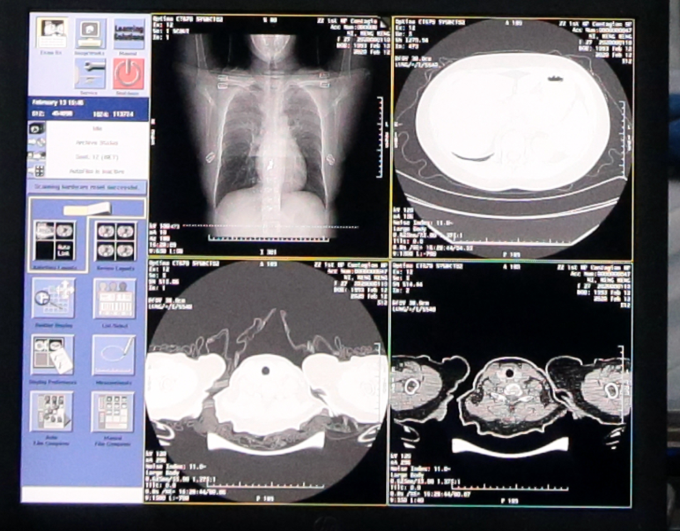

据介绍,新冠肺炎患者的CT胸片的影像特征表现为单肺或双肺多发、斑片状或节段性磨玻璃密度影等细微变化。

据了解,一位新冠肺炎病人的CT影像大概在300张左右,这给医生临床诊断带来巨大压力,医生对一个病例的CT影像肉眼分析耗时大约为5-15分钟。

通过NLP自然语言处理回顾性数据、使用CNN卷积神经网络训练CT影像的识别网络,AI可以快速鉴别新冠肺炎影像与普通病毒性肺炎影像的区别,最终识别准确率高达96%。

目前的技术成果是,AI每识别一个病例平均只需要不到20秒,大大提高诊断效率,减轻医生压力。此外,AI还能直接算出病灶部位的占比比例,进而量化病症的轻重程度,大幅提升临床诊断效率。